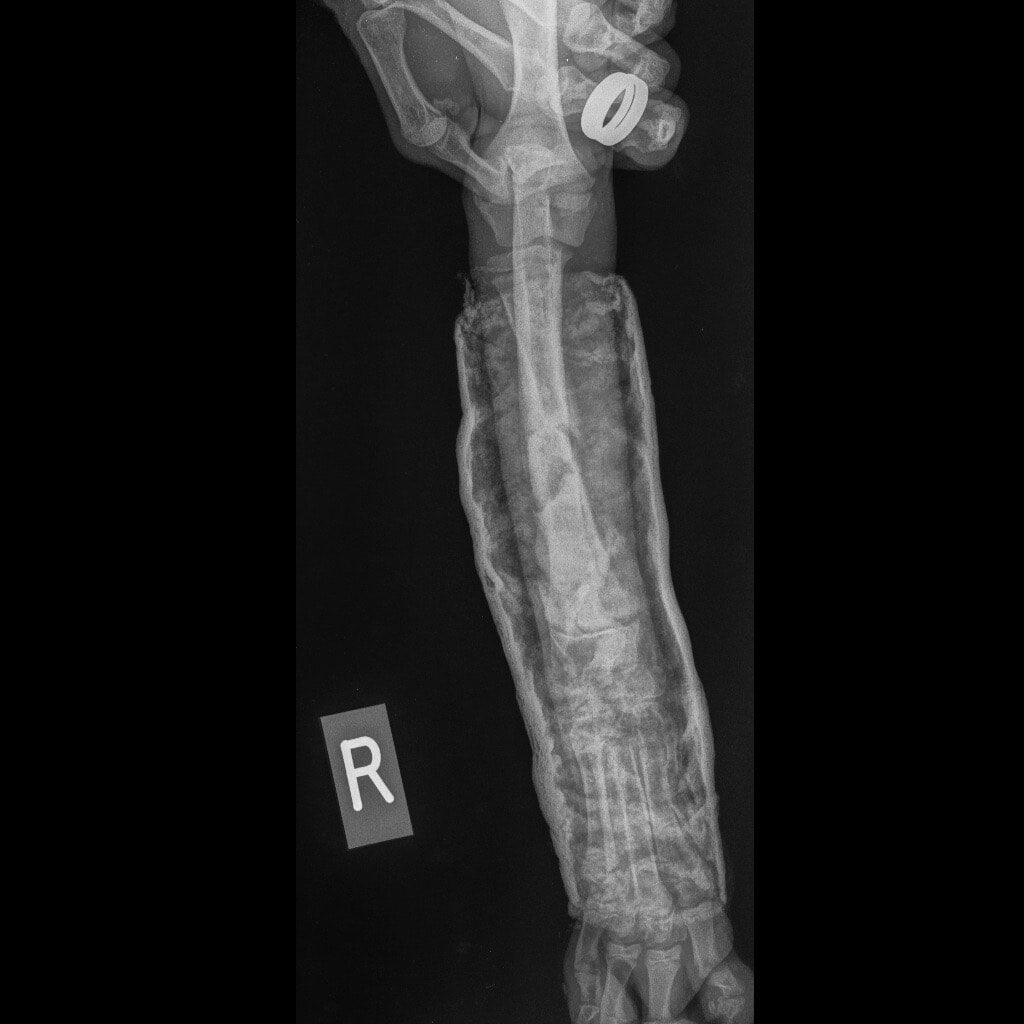

Ο Νικόλας βρέθηκε από εθελοντές και μεταφέρθηκε σε κτηνιατρείο. Δύο μπροστινά σπασμένα πόδια, πληγές, τσιμπούρια, ψύλλοι. Αυτή ήταν η κατάστασή του.

Η Maria Arkomani αναφέρει χαρακτηριστικά: «Δυστυχώς πολλοί ορθοπεδικοί έλειπαν και κάποιοι άλλοι δεν αναλάμβαναν το χειρουργείο του λόγω δυσκολίας και συγχρόνως επειδή είχαν περάσει μέρες από το σπάσιμο. Αμέσως πήγαμε στο κτηνιατρείο της Lena Kon για να δοθούν οι πρώτες βοήθειες από τον Νίκο Μαργαρίτη όπου τον ευχαριστούμε από καρδιάς. Βγήκαν ακτινογραφίες και έδειξαν τη ζημιά που είχε υποστεί αυτό το πλάσμα. Στο ένα πόδι μπήκε γύψος αλλά το άλλο ήθελε χειρουργείο. Στείλαμε σε πολλούς γιατρούς τις ακτινογραφίες αλλά οι απαντήσεις ήταν αρνητικές καθώς ήταν δύσκολο το χειρουργείο σε να κουτάβι με τέτοιο πρόβλημα. Ο μοναδικός γιατρός που μας απάντησε άμεσα και μπόρεσε να αναλάβει τον Νικόλα μας και να πάρει το ρίσκο του χειρουργείου είναι ο ορθοπεδικός Antonios Lionakis. Ένα χειρουργείο πάρα πολύ δύσκολο, με ρίσκο αλλά πρέπει να γίνει..»